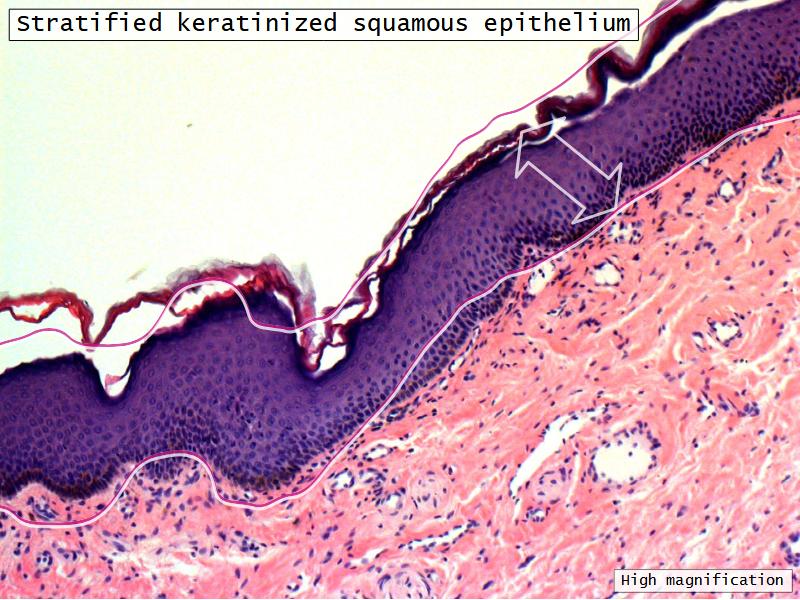

- Skin

Nostril